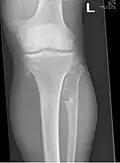

The diagnosis of HMO is based upon establishing an accurate correlation between the above-mentioned clinical features and the characteristic radiographic features. Family history can provide an important clue to the diagnosis. This is supplemented by testing for the two genes in which pathogenic variants are known to cause HMO namely EXT1 and EXT2. A combination of sequence analysis and deletion analysis of the entire coding regions of both EXT1 and EXT2 detects pathogenic variants in 70–95% of affected individuals.[3][7] The hallmark of radiographic diagnosis is the presence of osteochondromas at the metaphyseal ends of long bones in which the cortex and medulla of the osteochondroma represent a continuous extension of the host bone. This is readily demonstrable in radiographs of the knees.[3][1]

Multiple osteochondromas around the knee